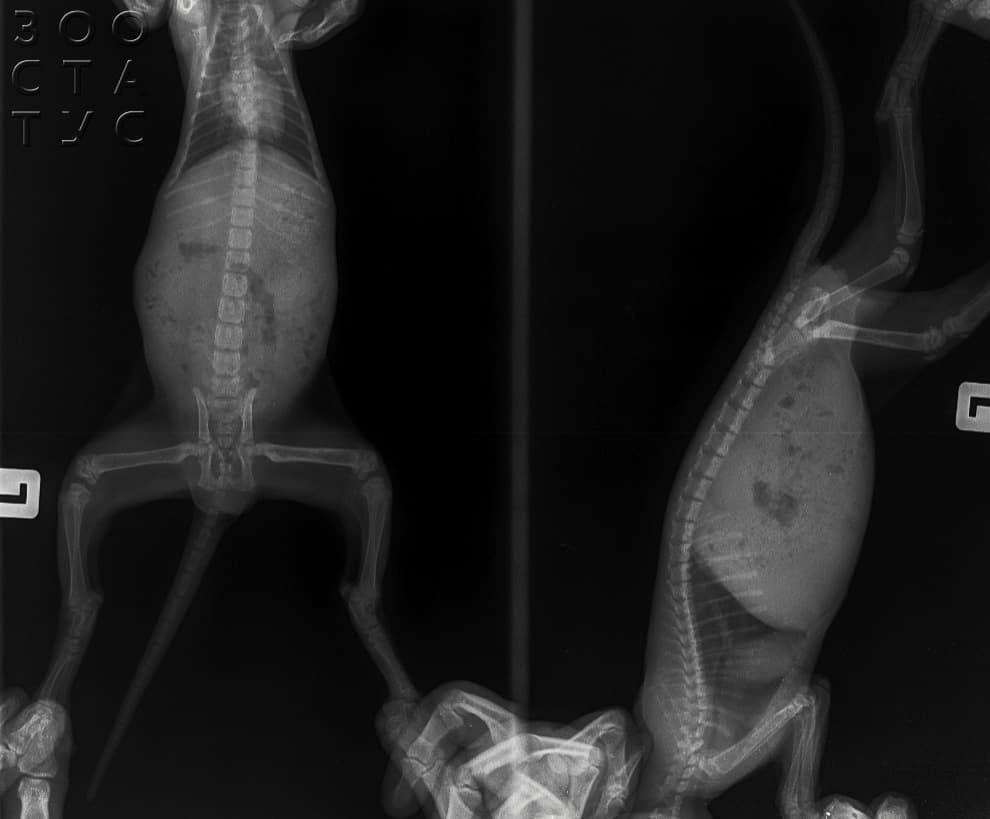

Диагноз ставится после клинического исследования, специалисты учитывают результаты лабораторных анализов крови, а при помощи рентгеновских снимков изучают состояние и строение костей, а именно: общую конфигурацию и степень их деформации.

Важным диагностическим тестом является рентгенография опорно-двигательного аппарата.

Выявляется плохая оссификация наиболее быстро растущих костей, расширение, деформация ростковых зон, деформация суставов. Типична угловая деформация конечностей из-за асинхронного роста костей.

Рентгенограммы обычно характерны для остеопении и помогают поставить окончательный диагноз. Обычно наблюдается булавовидное утолщение метафизов и сжатие эпифизов, а также деформации длинных костей, таких как проксимальный отдел плечевой кости, дистальный отдел лучевой кости, локтевой кости и ребер, с увеличением реберно-хрящевых соединений («рахитические четки»).